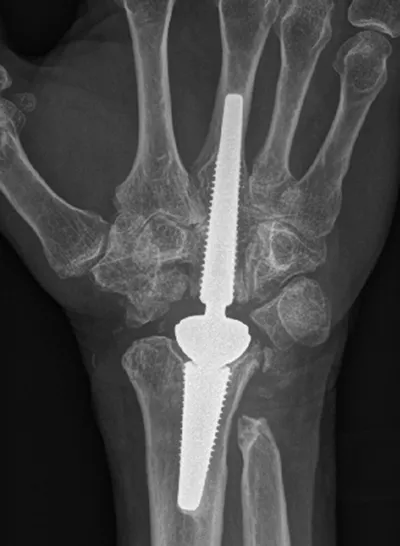

X-ray of a wrist with implant

In this procedure, the wrist joint is replaced with a metal joint – much like a small hip replacement. The advantage of this over a fusion is that you keep movement in the wrist. Government guidelines, from the National Institute for Clinical Excellence, are that wrist replacement’ should be undertaken only on carefully selected patients, by surgeons with special expertise in interventions for the hand and wrist… with special arrangements for clinical governance, consent and audit or research.’ With this in mind, if you do opt to have a wrist replacement, the expectation is that you will be contacted for long-term follow-up.